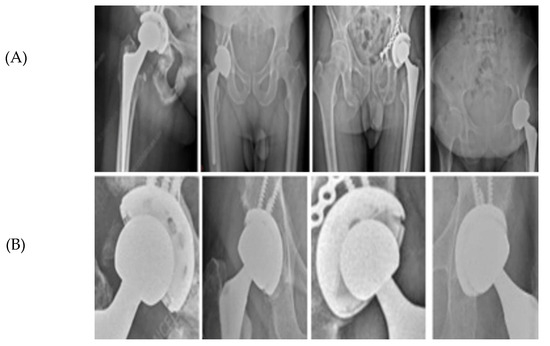

A Hybrid Automatic Model for Circle Detection in X-Ray Imagery: A Case Study on Hip Prosthesis Wear

This study presents a fully automatic hybrid framework for circle detection and geometric feature extraction from anteroposterior (AP) X-ray images. Detecting circular structures in X-ray imagery is challenging due to low contrast, noise, and metal-induced artifacts, which often limit the robustness of purely learning-based or purely geometric approaches. To address these challenges, a hybrid deep learning and computer vision pipeline is proposed that combines data-driven region localization with robust geometric fitting. A YOLOv5-based detector is first employed to identify a compact region of interest (ROI) containing circular components. Within this ROI, edge-based processing using Canny detection is applied, followed by an Edge-Snap refinement stage and robust RANSAC-based circle fitting with a Hough-transform fallback to ensure anatomically plausible circle estimation. The resulting circle centers and radii provide stable geometric parameters that can be consistently extracted across images with varying contrast, noise levels, and prosthesis appearances. The applicability of the proposed framework is demonstrated through a case study on hip prosthesis wear analysis, where the automatically detected circle parameters are used to compute medial, superior, and resultant displacement components using established two-dimensional radiographic formulations. Experimental evaluation on AP hip radiographs shows that the YOLOv5 detector achieves high ROI localization performance (mAP@0.5 = 0.971) and that the hybrid pipeline produces consistent circle parameters across longitudinal image sequences. Overall, the proposed method provides an end-to-end automatic solution for robust circle detection in X-ray imagery, with hip prosthesis wear presented solely as a case study without clinical or diagnostic claims. Full article